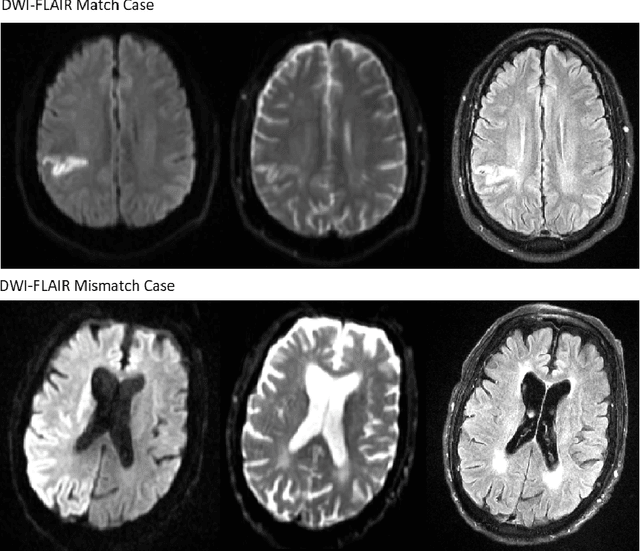

Abstract:Treatment of acute ischemic strokes (AIS) is largely contingent upon the time since stroke onset (TSS). However, TSS may not be readily available in up to 25% of patients with unwitnessed AIS. Current clinical guidelines for patients with unknown TSS recommend the use of MRI to determine eligibility for thrombolysis, but radiology assessments have high inter-reader variability. In this work, we present deep learning models that leverage MRI diffusion series to classify TSS based on clinically validated thresholds. We propose an intra-domain task-adaptive transfer learning method, which involves training a model on an easier clinical task (stroke detection) and then refining the model with different binary thresholds of TSS. We apply this approach to both 2D and 3D CNN architectures with our top model achieving an ROC-AUC value of 0.74, with a sensitivity of 0.70 and a specificity of 0.81 for classifying TSS < 4.5 hours. Our pretrained models achieve better classification metrics than the models trained from scratch, and these metrics exceed those of previously published models applied to our dataset. Furthermore, our pipeline accommodates a more inclusive patient cohort than previous work, as we did not exclude imaging studies based on clinical, demographic, or image processing criteria. When applied to this broad spectrum of patients, our deep learning model achieves an overall accuracy of 75.78% when classifying TSS < 4.5 hours, carrying potential therapeutic implications for patients with unknown TSS.